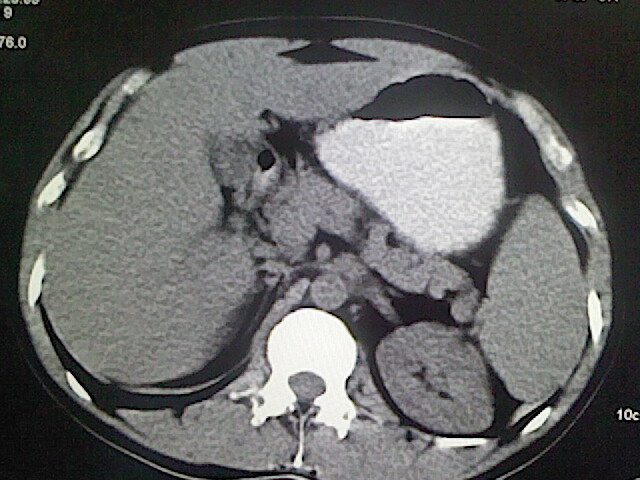

以下是引用卜一在2009-3-14 9:49:00的发言:[br]胆囊萎缩,胆囊壁不规则增厚,内部结构模糊,增强明显强化。另:肝左叶外侧段肝囊肿。支持:慢性胆囊炎!高度可疑:胆囊癌!

以下是引用余辉在2009-3-14 8:48:00的发言:[br]1)慢性胆囊炎。2)肝左叶外侧段肝囊肿。3)脂肪肝。[br]支持,胆囊萎缩,密度增高,不知b超具体有何提示,钙胆汁?结石?

以下是引用jiangjing在2009-3-14 10:18:00的发言:[br]1)慢性胆囊炎。2)肝左叶外侧段肝囊肿。3)脂肪肝。4.】建议行肝功能检查